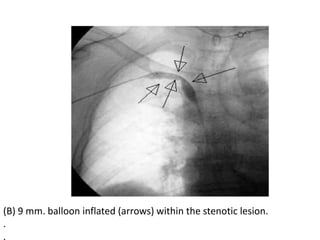

(B) 9 mm. balloon inflated (arrows) within the stenotic lesion.

.

(B) 9 mm.balloon inflated (arrows) within the stenotic lesion. . .